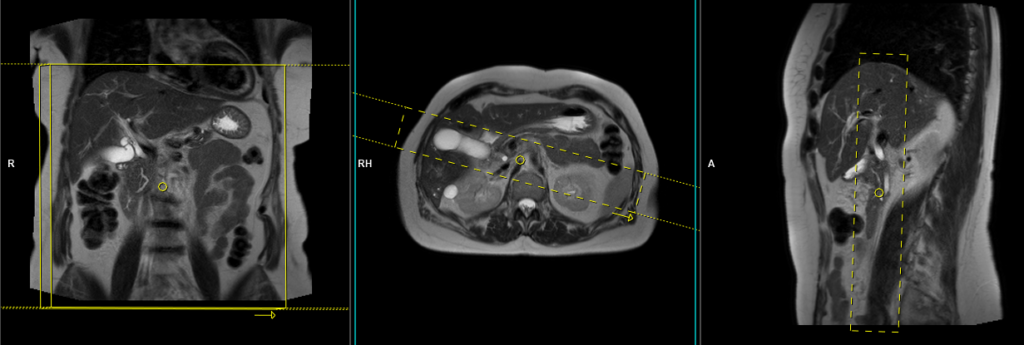

T2 SPACE 3D(or T2 TSE) coronal respiratory gated 1MM

Plan the coronal 3D sequence on the axial HASTE scan. Position the block across the common bile duct and pancreatic duct. Verify the positioning in the other two planes. Establish an appropriate angle in the sagittal plane, aligning it horizontally across the bile duct. Ensure that the slices adequately cover the entire common bile duct, pancreatic duct, and gall bladder. Use phase oversampling to prevent wrap-around artifacts.

For respiratory gated scans, it is crucial to accurately position the respiratory navigator box. Place it in the middle of the right dome of the diaphragm, with half of the box over the right lobe of the liver (segment 8) and the other half over the lungs. Planning should be performed in a non-breath hold localizer, as the diaphragm pushes down the liver during inhalation, which can lead to improper slice planning and positioning of the respiratory navigator box.

Instruct the patient to breathe gently throughout the sequence. Very shallow or erratic breathing can reduce the effectiveness of the navigator.

Parameters

TR 2500-3000 | TE 500-700 | FLIP 12 | NEX 1 | SLICE 1MM | MATRIX 320X320 | FOV 350 | PHASE R>L | OVERSAMPLE 50% | IPAT ON |